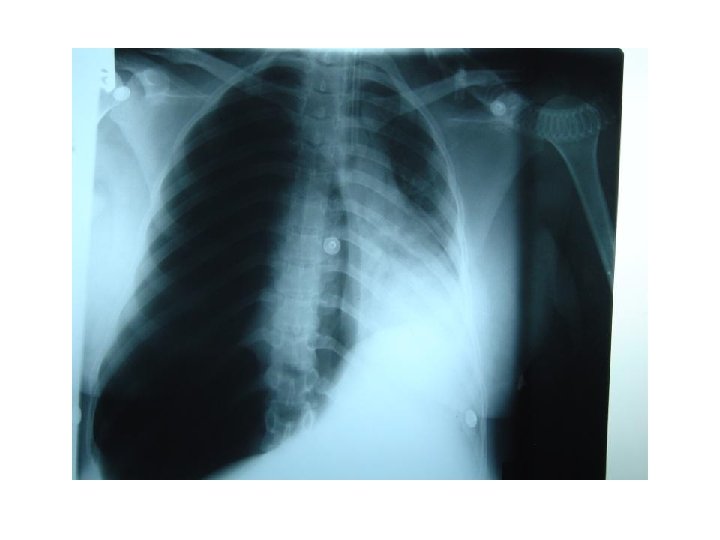

Trauma. . ﺑﻌﺪ ﻛﺪﺍ ﻣﺎ ﺷﺮﺡ ﺍﻟﺪﻛﺘﻮﺭ § § § RTA Fracture Ribs Simple – Complicated Haemothorax Pneumothorax Flail chest Lung Contusion and ARDS

Flial Chest